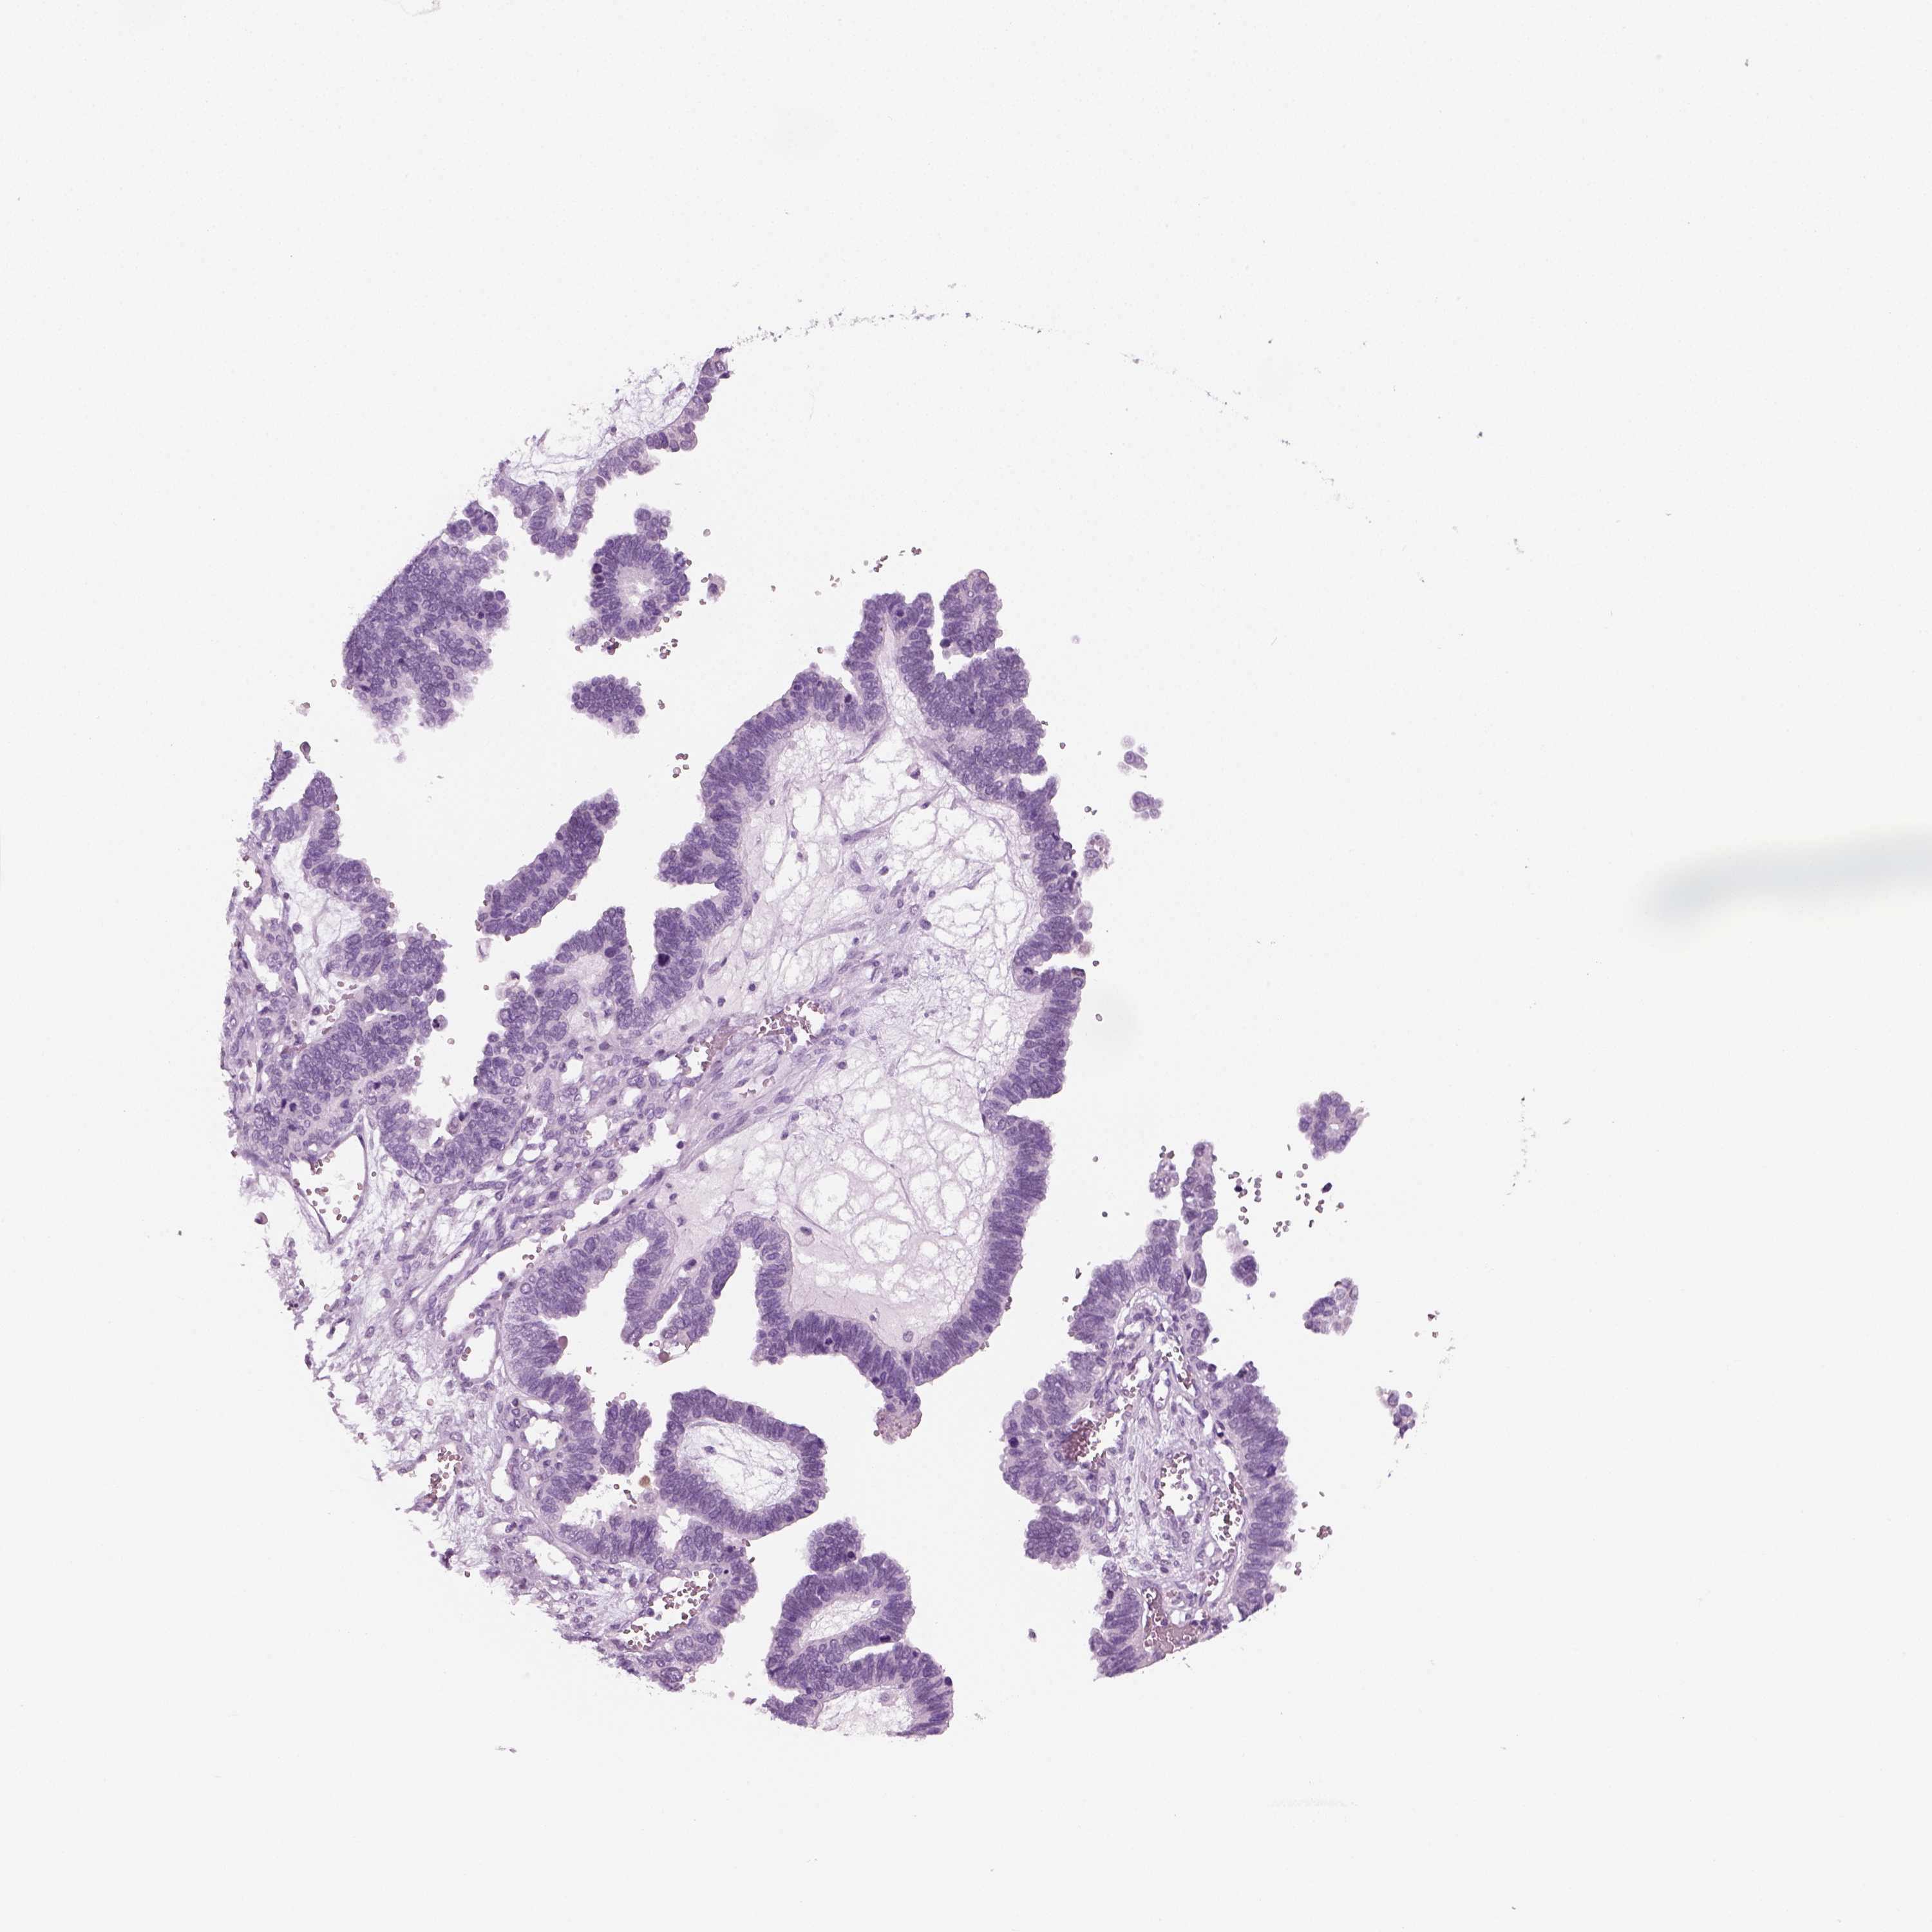

OVARIAN CANCER - Protein expressioni

A mouse-over function shows sample information and annotation data. Click on an image to view it in a full screen mode. Samples can be filtered based on level of antibody staining by selecting one or several of the following categories: high, medium, low and not detected. The assay and annotation is described here.

Note that samples used for immunohistochemistry by the Human Protein Atlas do not correspond to samples in the TCGA dataset.

Antibody stainingi

Antibody staining in the annotated cell types in the current human tissue is reported as not detected, low, medium, or high, based on conventional immunohistochemistry profiling in selected tissues. This score is based on the combination of the staining intensity and fraction of stained cells.

Each image is clickable and will lead to virtual microscopy that enables deeper exploration of all samples and also displays staining intensity scores, fraction scores and subcellular localization as well as patient and tissue information for each sample.

Antibody HPA019367

Antibody HPA076201

Cystadenocarcinoma, mucinous, NOS

Carcinoma, endometroid